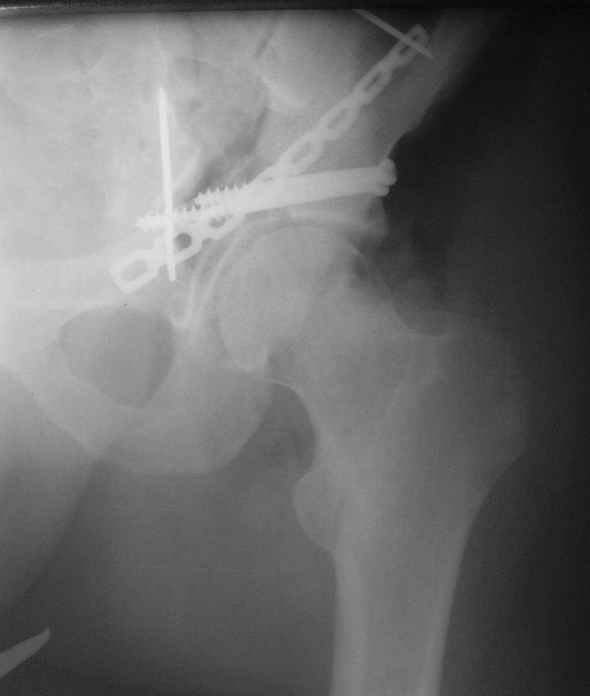

Высылаю пример еще одного случая, остеосинтез пластиной из подвздошного доступа.